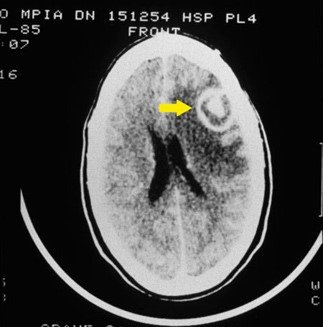

큰 주머니안에 기생충으로 보이는 것들이 있었다(위 사진)

알고보니 그 기생충들은 쥐나 토끼에서 발견되어 '톡소포자충'이라고 붙여진것

이 사진은 톡소포자충에의한 뇌종양 사진입니다.